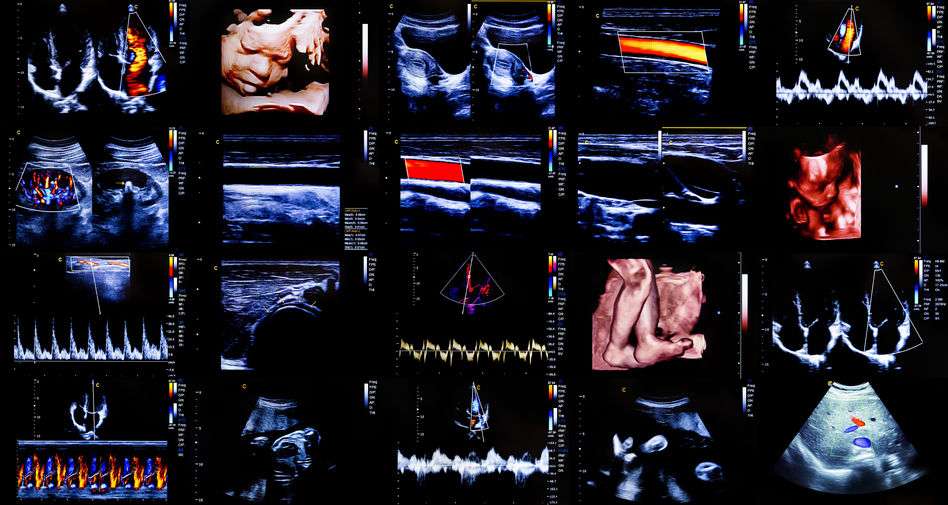

B超这种检查项目,除了在孕期发挥出巨大作用外,有很多其他疾病也可通过B超筛查发现,比如我国较为高发的脂肪肝、子宫肌瘤、肝肾损伤、泌尿系统疾病等。

正因如此,B超也成为了常规体检项目中的一项,无论男女都可进行B超筛查!